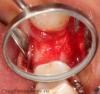

pit Опубликовано 13 декабря, 2012 Поделиться Опубликовано 13 декабря, 2012 у меня прекрасные результаты на ксенографтах, у Бузера кстати тоже ))вопрос веры, не более.Олег! У тебя есть фотки МР3 в ране через 4-6 мес после аугментации ? Ссылка на комментарий

Bier Опубликовано 14 декабря, 2012 Автор Поделиться Опубликовано 14 декабря, 2012 (изменено) Олег! У тебя есть фотки МР3 в ране через 4-6 мес после аугментации ?есть! но пока не покажу ) впрочем небольшой спойлер можно, без комментариев. Изменено 14 декабря, 2012 пользователем Bier добавил картинку ) Ссылка на комментарий